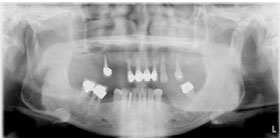

治療前X光片,多處缺牙及嚴重牙周破壞。